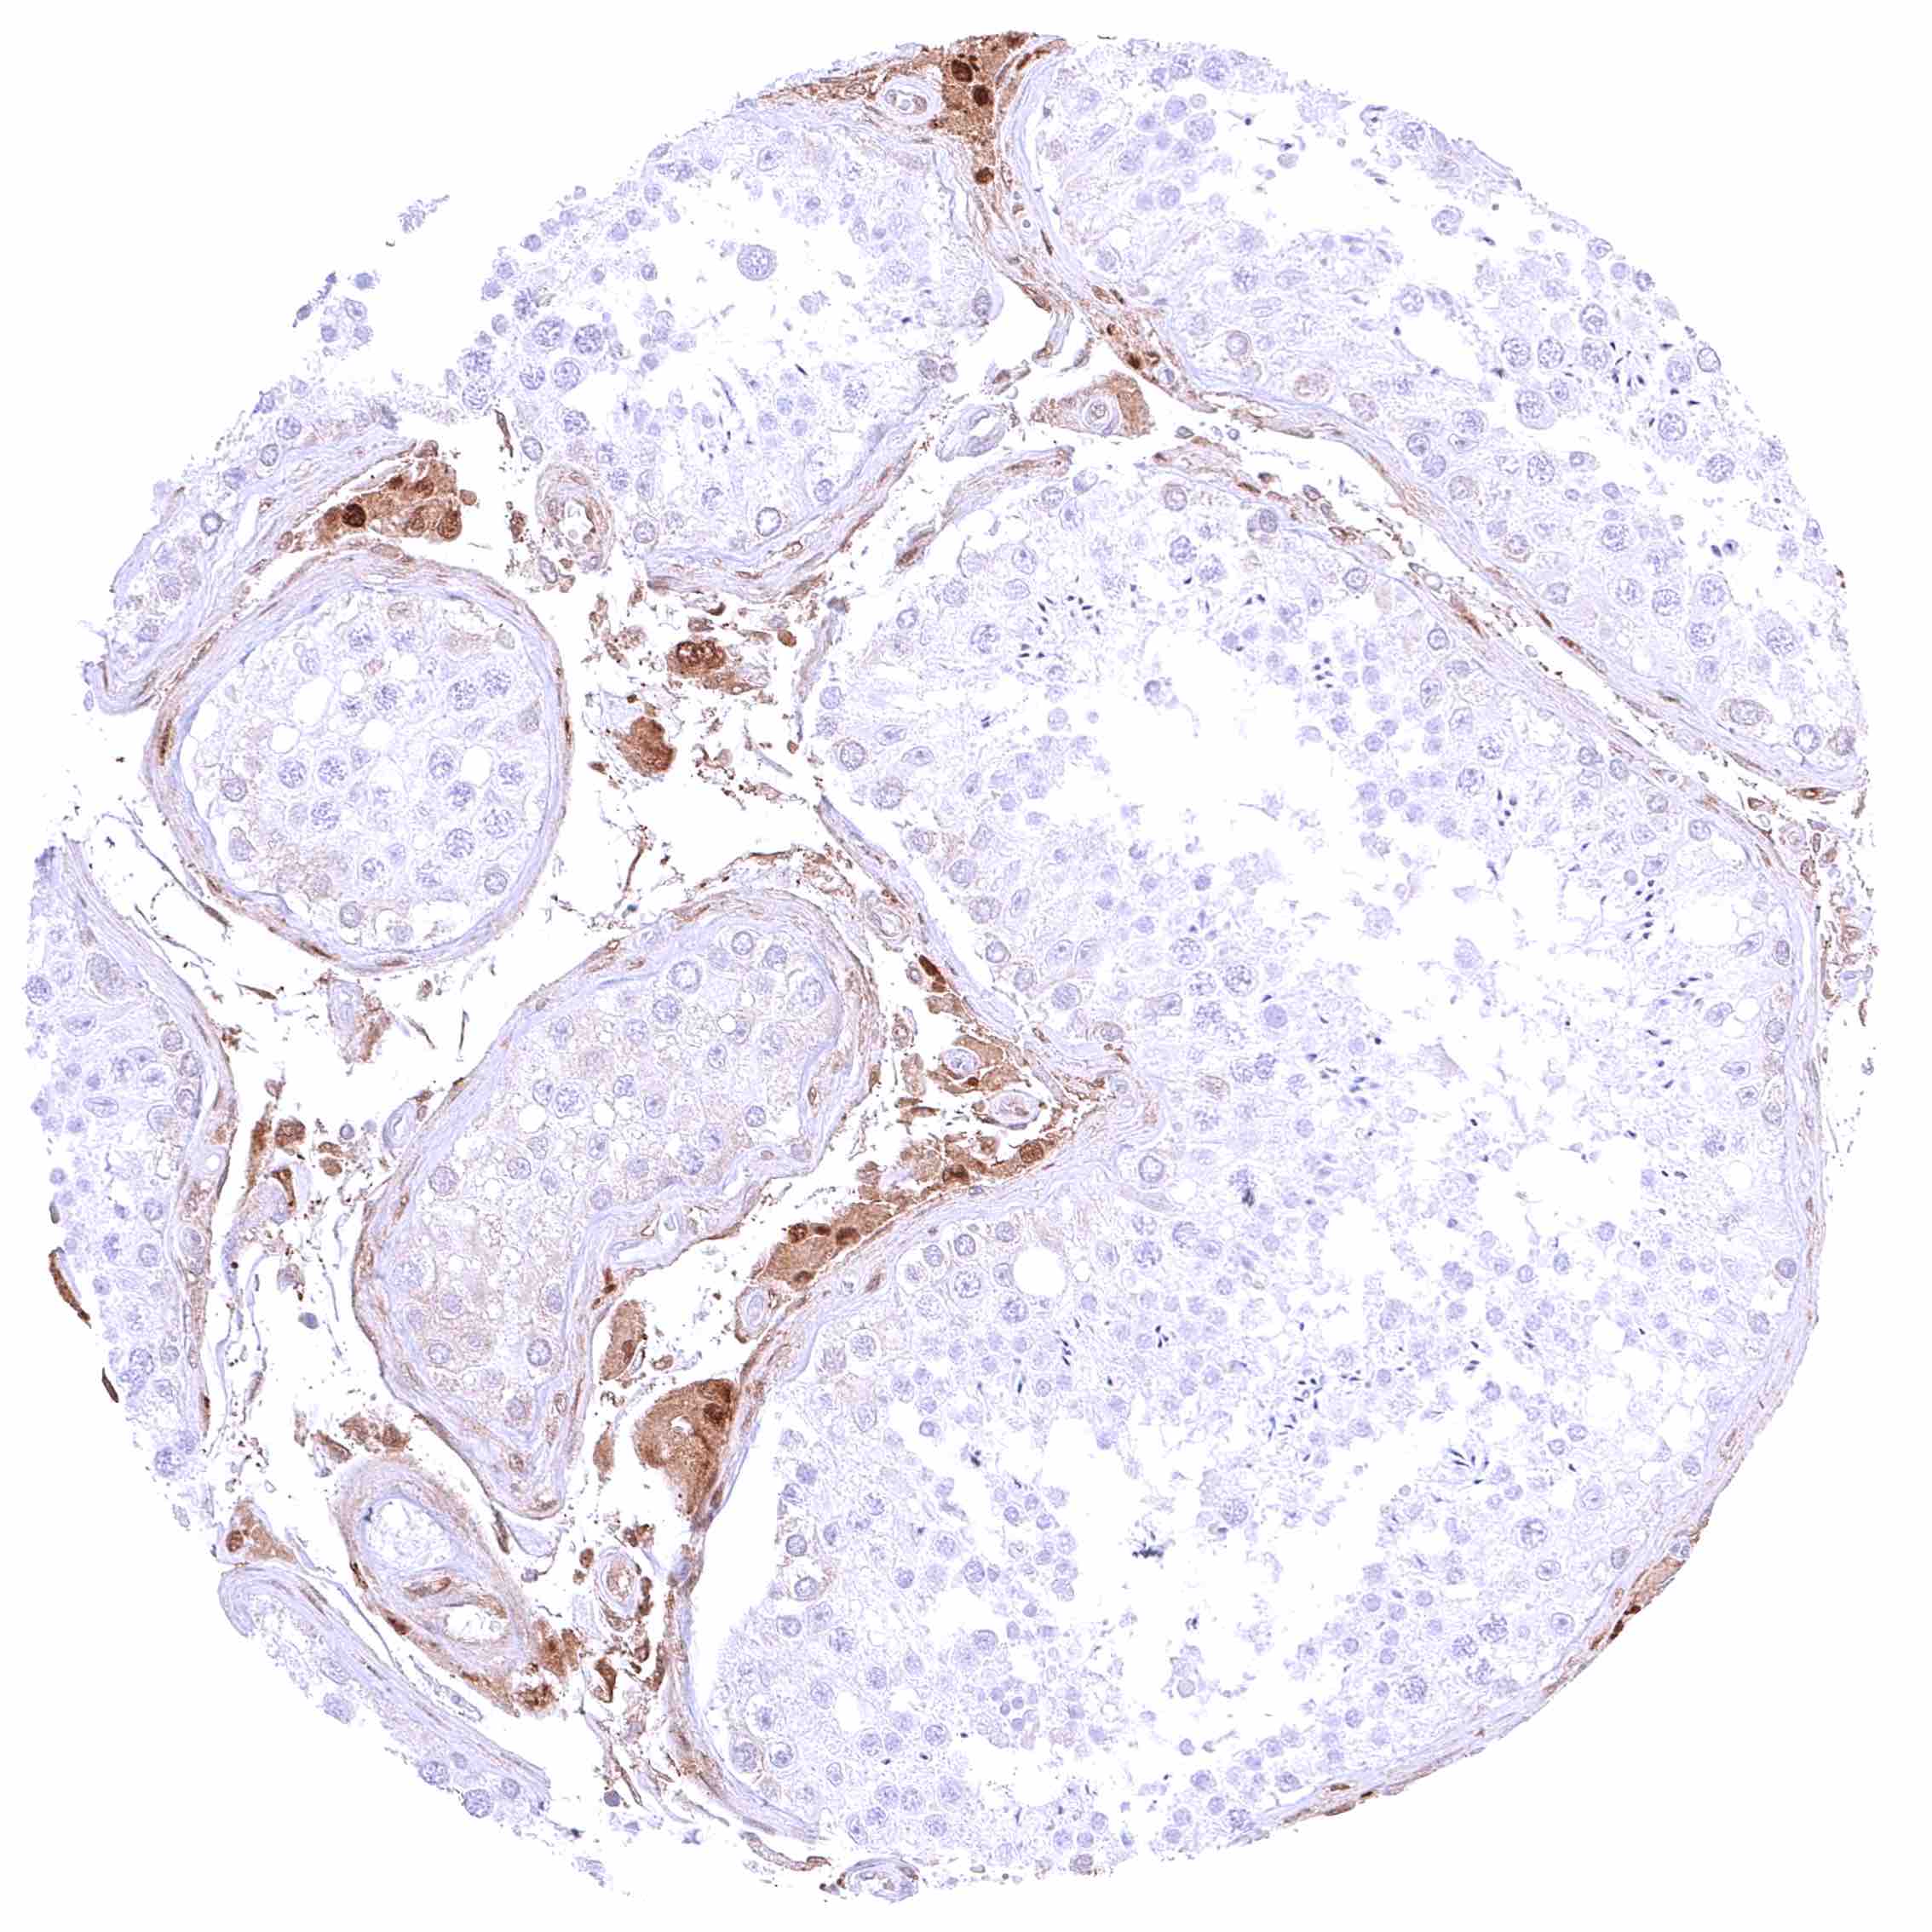

Prostate – Intense nuclear and cytoplasmic GSTP1 staining of basal cells while staining is faint or absent in acinar cells

Prostate – Intense nuclear and cytoplasmic GSTP1 staining of basal cells while staining is faint, weak or even absent in acinar cells